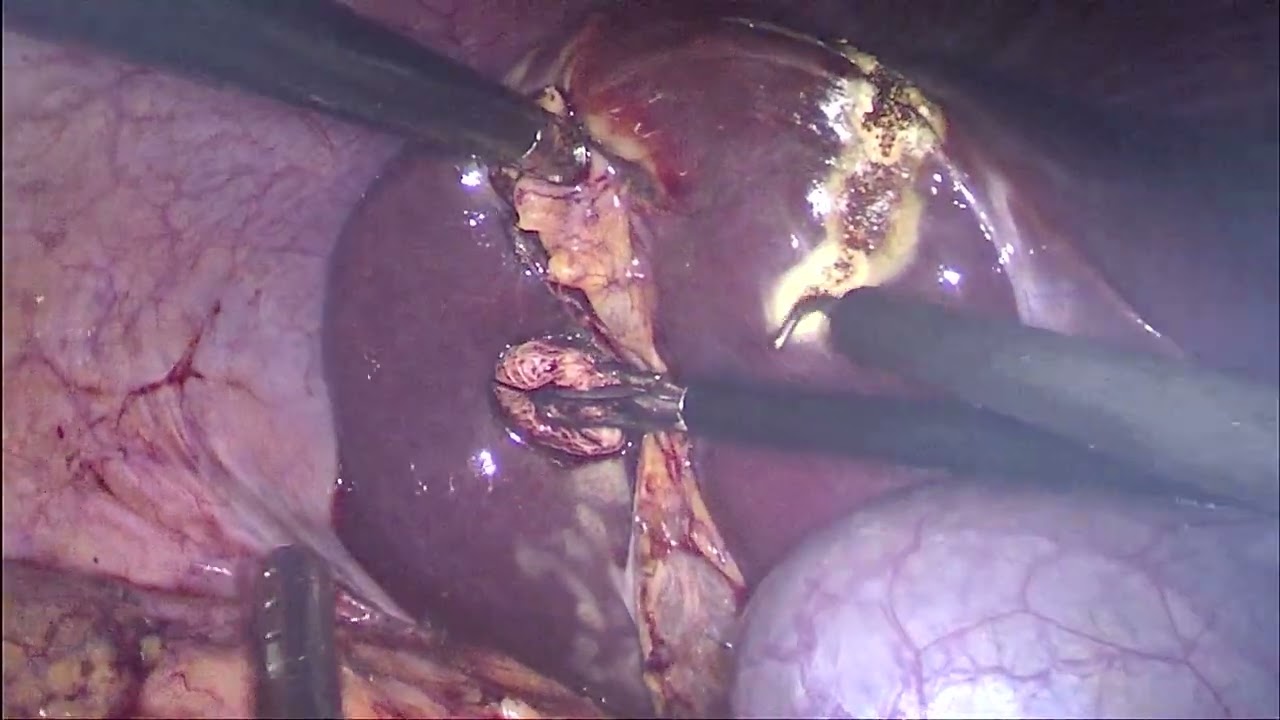

El Dr Augusto J. Carrié es cirujano especialista en cirugía colorrectal y general. Es experto en Cirugía Laparoscópica del Cáncer de Colon y Recto, Enfermedad Diverticular y Patologías Piso Pelviano.

El Dr. Augusto j. Carrié obtuvo su titulo de médico en la Universidad de Buenos Aires (UBA), completo su residencia de cirugía general en el CEMIC. Fue Acreditado por la Asociación Argentina de Cirugía (AAC) en Cirugía Videoendoscópica y Mininvasiva. Parte de su subespecialización en cirugía colorrectal laparoscópica y mínimamente invasiva fue desarrollada en reconocidas instituciones internacionales como lo son Norwalk Hospital, Connecticut, Jackson Hospital, Florida y Celebration Hospital, Florida. Actualmente se desempeña como Jefe del la Sección de Cirugía General en el CEMIC.

El Dr. Augusto J. Carrié cree que el abordaje mínimamente invasivo de la patología colorrectal es un gran avance para los pacientes con enfermedades del colon y recto.

• Cirugía laparoscópica avanzada